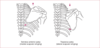

Colles Fracture

Distal radius fragment is dorsally displaced (CD). Associated with triangular fibrocartilage complex (TFCC) tears.